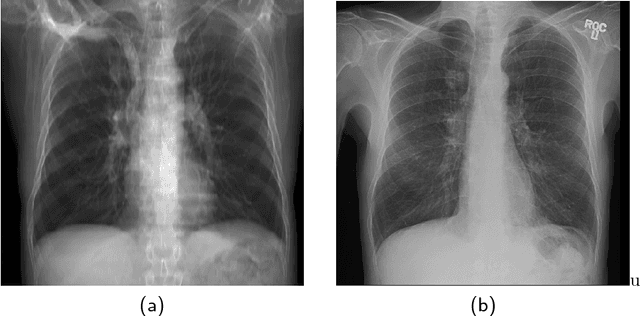

Abstract:The abundance of overlapping anatomical structures appearing in chest radiographs can reduce the performance of lung pathology detection by automated algorithms (CAD) as well as the human reader. In this paper, we present a deep learning based image processing technique for enhancing the contrast of soft lung structures in chest radiographs using Fully Convolutional Neural Networks (FCNN). Two 2D FCNN architectures were trained to accomplish the task: The first performs 2D lung segmentation which is used for normalization of the lung area. The second FCNN is trained to extract lung structures. To create the training images, we employed Simulated X-Ray or Digitally Reconstructed Radiographs (DRR) derived from 516 scans belonging to the LIDC-IDRI dataset. By first segmenting the lungs in the CT domain, we are able to create a dataset of 2D lung masks to be used for training the segmentation FCNN. For training the extraction FCNN, we create DRR images of only voxels belonging to the 3D lung segmentation which we call "Lung X-ray" and use them as target images. Once the lung structures are extracted, the original image can be enhanced by fusing the original input x-ray and the synthesized "Lung X-ray". We show that our enhancement technique is applicable to real x-ray data, and display our results on the recently released NIH Chest X-Ray-14 dataset. We see promising results when training a DenseNet-121 based architecture to work directly on the lung enhanced X-ray images.